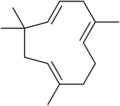

Let's start with some background on marijuana chemistry. Relevant chemicals in marijuana fall into two broad classes: cannabinoids (which in plants are specific to the Cannabis genus) and terpenoids (which are widespread in many plants).[7][8] Humans and other animals, produce endocannabinoids, which are different than but in the same chemical class as those cannabinoids found in cannabis. The main psychoactive chemical in marijuana is tetrahydrocannabinol (THC). Another important cannabinoid is cannabidiol (CBD), which is not psychoactive but has many claimed health benefits. Terpenoids in cannabis include ocimene, myrcene, β-caryophyllene, limonene, pinene, myrcene, linalool.